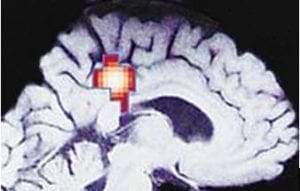

IPT for patients ill with depression,6 even without medication, causes the area of the brain known as the cingulum or cingulate gyrus to activate as patients recover. Developing from the primitive limbic system for memory and emotion, it is far more advanced in humans in size and complexity. The front is responsible for regulating emotional tone. When damaged or not functioning properly, it can cause depression, anger, anxiety, and irrational obsessions. The back of the cingulum knits together thinking and emotional tone. With IPT there is an increase in activity, even without medication, as a patient progresses from a state of clinical depression to recovery: (fig 3) the cingulum is activated as contentment grows, as rationality increases, and as anxiety and suspicion diminishes. Adding this type of psychotherapy to antidepressants in severely depressed individuals7 also altered nerve dopamine receptors more than medication alone, with associated clinical improvement.